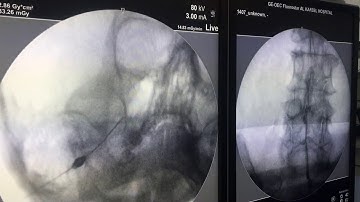

Gasserian ganglion Trigeminal block - made simplified by demo on the skull